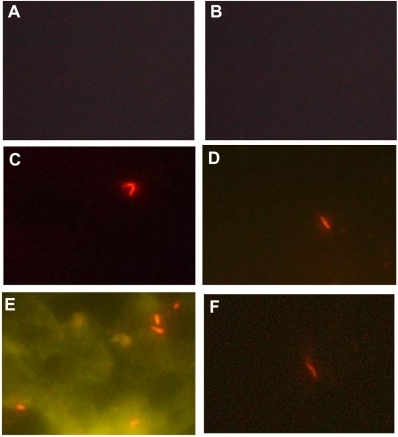

Histology of tuberculosis (TB) shows caseating granulomas, and positive acid-fast bacilli (AFB) stain.